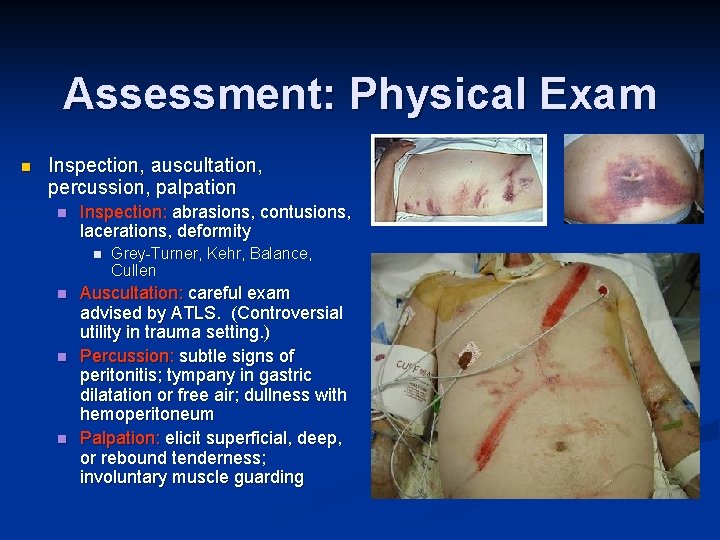

Assessment: Physical Exam n Inspection, auscultation, percussion, palpation n Inspection: abrasions, contusions, lacerations, deformity n n Grey-Turner, Kehr, Balance, Cullen Auscultation: careful exam advised by ATLS. (Controversial utility in trauma setting. ) Percussion: subtle signs of peritonitis; tympany in gastric dilatation or free air; dullness with hemoperitoneum Palpation: elicit superficial, deep, or rebound tenderness; involuntary muscle guarding